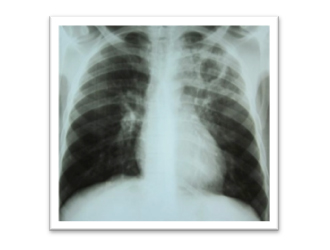

Yes. Your doctor would advice appropriate test after examining you. It may include Chest X-ray, Sputum Test, CT scan of Chest etc.